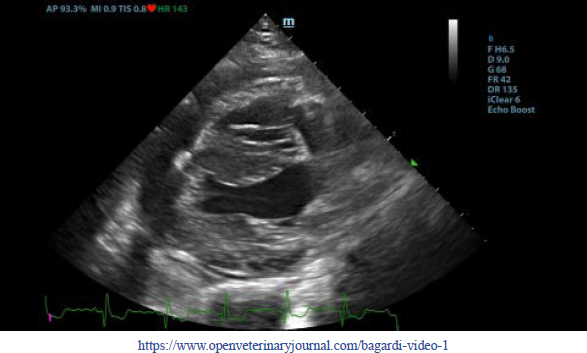

First, transthoracic echocardiogram findings were a small amount of circumferential tamponating pericardial effusion (Fig. 1) and a severe hyperechoic pericardial thickening (10.2 mm) (Fig. 2). The right atrium was normal in size and there was collapse during systole. There was mild septal flattening seen on short axis view of the left ventricle. A short-axis left ventricular M-mode showed posterior displacement of the interventricular septum during late diastole at the time of atrial systole (Fig. 3). The epicardium and pericardium had a hyperechoic appearance with a thin, shaggy layer of heterogeneous echogenic material lining the surface of each (Fig. 1, Supplementary Video I). Pericardiocentesis was not recommended at this time given that the patient was minimally clinically and hemodynamically affected. Few hours later, a second echocardiographic examination, after stabilization of left ventricular volume with intravenous (IV) lactate ringer solution at maintenance rate, showed a worsening of pericardial thickness (13 mm) and an increase in pleural effusion. Furthermore, there was a >25% mitral inflow variation noted with respiration. In addition, there was >30% tricuspid inflow variation with respiration, signs of CP. During the second echocardiography, the patient appeared to be slightly dyspneic due to the increased thoracic effusion.

Fig. 2. Transthoracic echocardiogram – left apical five-chambered view. Note the pericardial effusion (white arrowhead) and the severe pericardial thickening (white arrow). Ao: aorta; LA: left atrium; LV: left ventricle; RA: right atrium; and RV: right ventricle.

Supplementary Video II. Transthoracic echocardiogram 2 days after discharge – right parasternal long-axis four-chambered view. Note the complete resolution of the pericardial effusion, the normal thickness of the pericardium, and normalization of the left ventricle volumes.